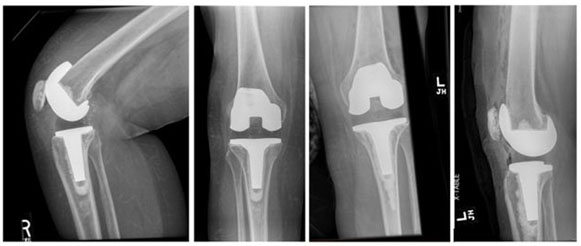

In both procedures, we utilized the previous midline anterior skin incision and medial parapatellar arthrotomy. The inflamed, fibrotic synovium was debrided and sent to pathology. Our concern for periprosthetic joint infection was low given clear joint fluid and low inflammatory markers, and we did not pursue fungal workup or send additional cultures. The femoral and tibial components were removed with minimal blood loss. Synovial biopsies were found to have wear debris, synovial fibrosis, and a histiocytic reaction, consistent with a type IV allergic reaction. Polyethylene articular surfaces were examined as a potential source of wear debris and showed unusually high wear at only two years (Figure 2). The new Sigma PS components were cemented into place, and the postoperative radiographs demonstrated excellent alignment (Figure 3).

Figure 3: Left and right anteroposterior radiographs post-operative to revision total knee arthroplasty show well-fixed TKA with proper alignment.